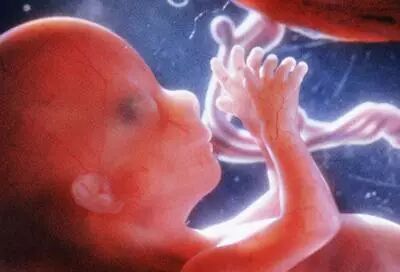

一个月:

标志着胚胎期的开始。身长约0.2厘米,体重约1克,。动脉、静脉已形成,且有血液流动;脑、肾、消化管已见雏形;脐带已开始工作;心脏形成且开始跳动。